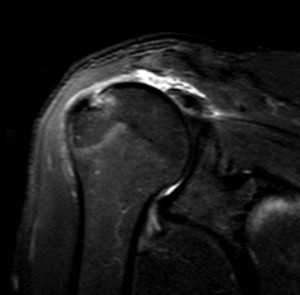

Разрыв вращательной манжеты - также характерное повреждение области плеча - может быть связан как с травмой, так и дегенеративными процессами. Разрывы вращательной манжеты бывают полные и неполные. Кроме того, по МРТ плечевого сустава выделяют 3 градации, в основе которых лежит не только изменение сигнала на Т2-зависимых томограммах, но и морфологические изменения сухожилия.

МРТ. Корональная Т2-зависимая томограмма с подавлением сигнала от жира. Полный разрыв сухожилия надостной мышцы.

При МРТ плечевого сустава косвенным признаком разрыва вращательной манжеты служит высокий сигнал на Т2-взвешенных от поверхности сустава до субакромиальной (субдельтовидной) сумки. Частичные разрывы чаще всего по передней поверхности сухожилия м.supraspinatus, реже примыкая к большой бугристости или сухожилия м. infraspinatus.